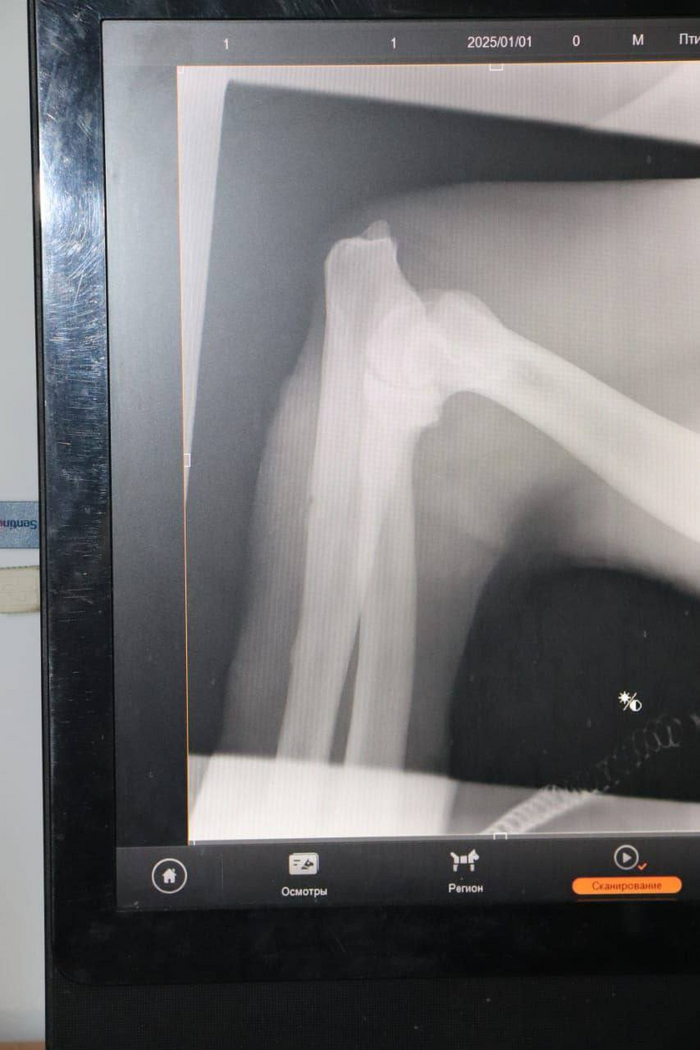

В центре реабилитации МРОО «Центр «Тигр» ветврачи осмотрели тигра (отловленного возле села Андреевка Хасанского района Приморского края).

Это взрослый самец 5-7 лет и весом 168 кг. У животного выявлены множественные раны мягких тканей различной давности: старые воспалённые, а также свежие. Предположительно, они получены в схватках с другими тиграми.

В дикую природу тигр пока не возвращается, остаётся в центре реабилитации. Надо подлечиться. Дальнейшую судьбу тигра решит Росприроднадзор.